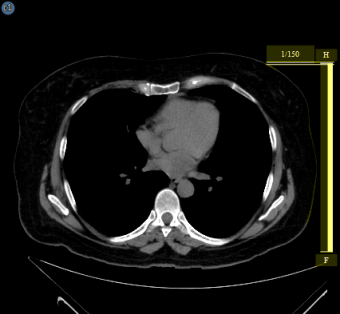

A halmazvonalzó megmutatja, hogy az aktuális kép hol helyezkedik el a sorozat többi képéhez képest. A halmazvonalzó overlay-ként jelenik meg a képkocka széle mentén, és mutatja az aktuálisan megjelenített kép relatív pozícióját a sorozaton belül. Az alábbi képen sárga színnel kiemelve jelenik meg.